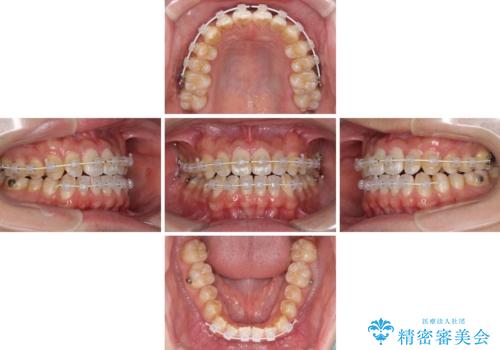

下顎前歯と上顎の部分矯正

- 矯正装置

- 審美装置

- 1年

- 10-30回

- 上下の前歯の叢生を気にして来院された患者様です。

前歯のみの矯正治療を希望でしたが、上顎臼歯が舌側転位していたため、上顎は全体を、下顎は前歯のみを矯正治療することとしました。

矯正治療は上下全顎を行うことが大前提ですが、費用などの点から、今回は部分矯正を選択することとなりました。

患者様本人は咬みにくさを感じていないようですが、部分矯正は咬み合わせの改善が困難であることが多く、咬みにくさが残ることがあります。